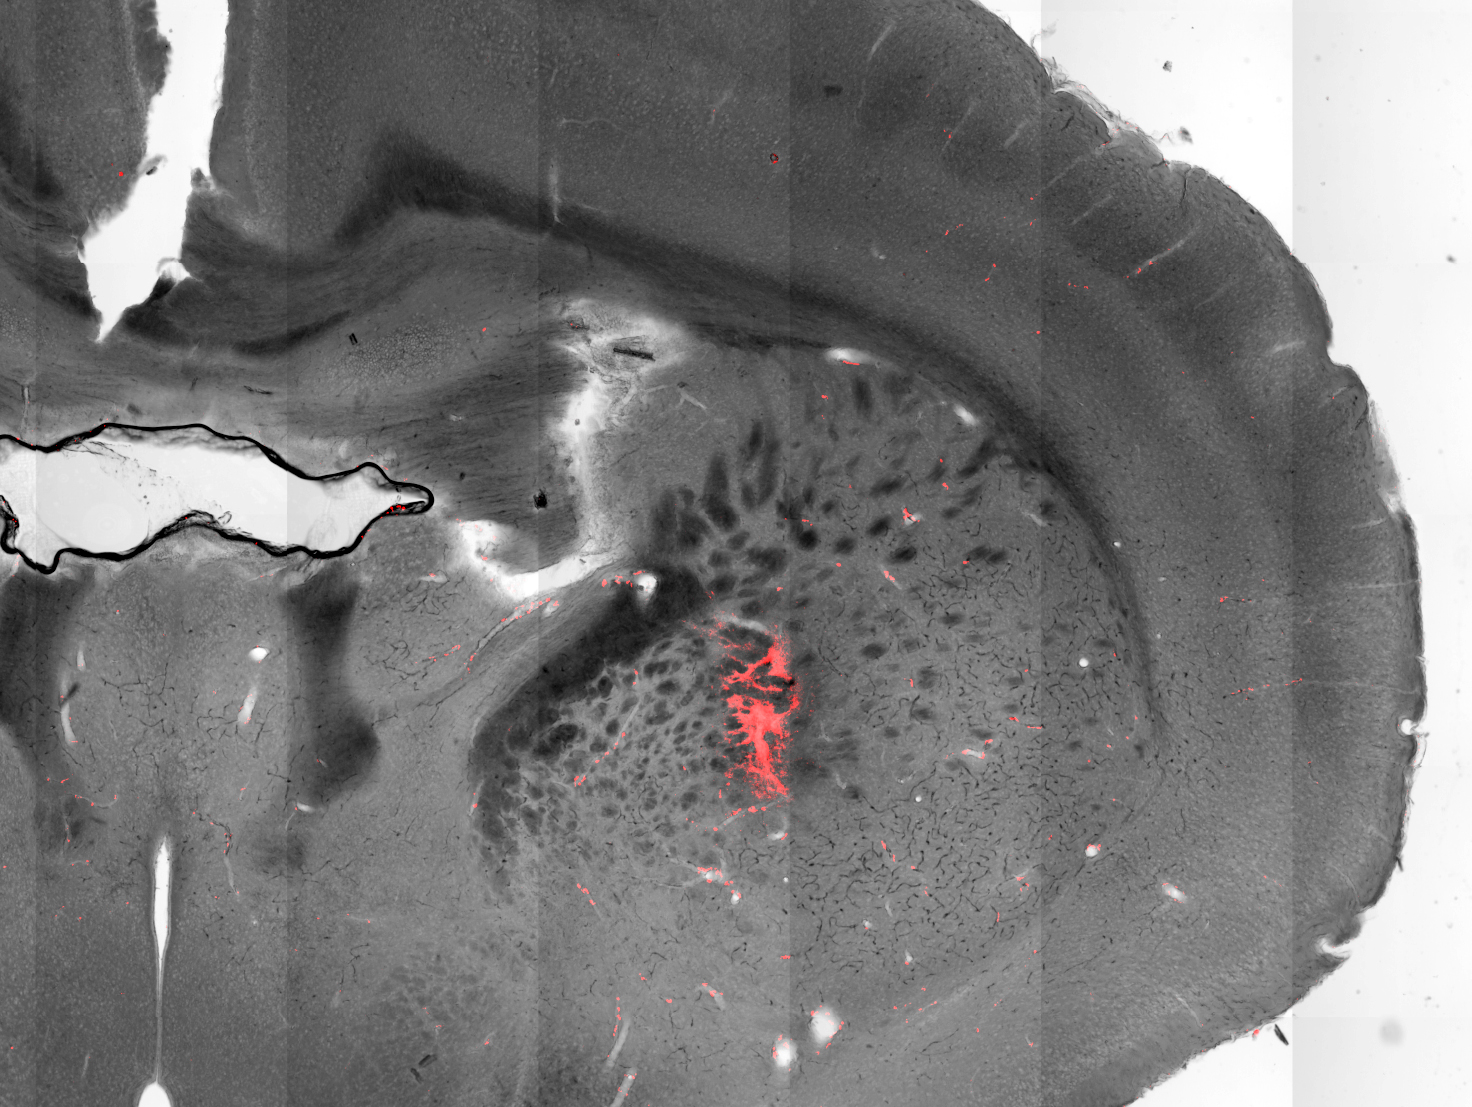

These results were achieved working with mice that had been genetically engineered such that targeted neurons would produce ion channels sensitive and even receptive to temperature. Nanoparticles consisting of a cobalt-ferrite core coated in manganese ferrite were injected into the brain, attaching themselves to neurons.

Applying an alternating magnetosphere causes the magnetization of these nanoparticles to switch back and forth, raising their temperature. As a result, the ion channels open up, causing the associated neurons to fire.